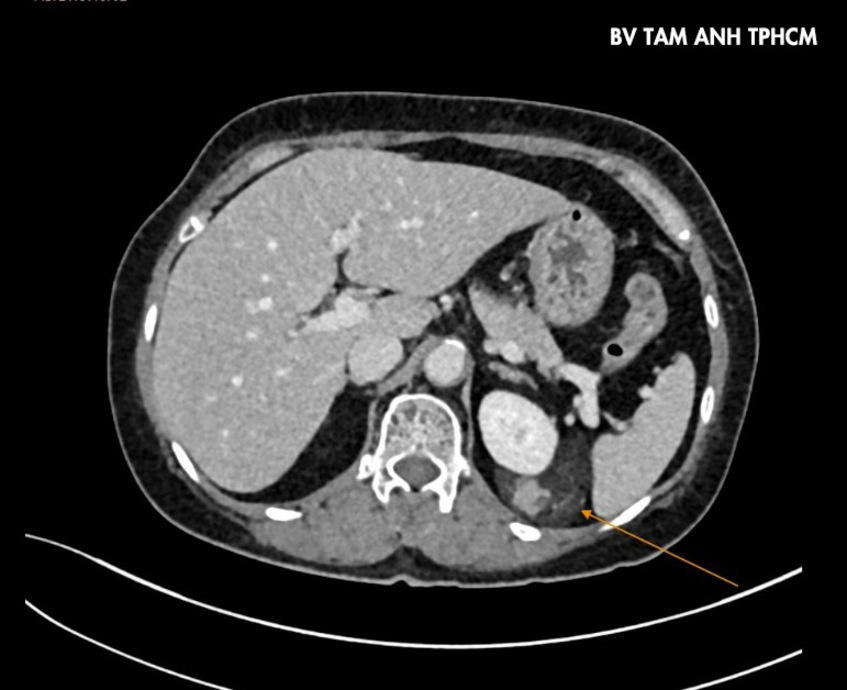

Trước đó, bà Kim, 63 tuổi, đến Bệnh viện Đa khoa Tâm Anh TP.HCM khám sức khỏe định kỳ, tình cờ phát hiện có khối u ở thận trái, kích thước khoảng 4×8 cm. Người bệnh không đau, không sốt, không tiểu máu. Hình ảnh chụp cắt lớp vi tính CT scan cho thấy khối u xuất phát từ một phần nhu mô thận rồi lan rộng ra xung quanh, bao lấy thận, kèm theo nhiều mạch máu tăng sinh dị dạng, khả năng là u cơ mỡ mạch thận (AML), một loại u thận lành tính.

Theo bác sĩ Cương, những khối u cơ mỡ mạch thận dưới 4 cm thường không gây triệu chứng và rất hiếm khi chảy máu, người bệnh chỉ cần theo dõi định kỳ. Tuy nhiên, trường hợp của bà Kim, khối u lớn đường kính đã gần 8 cm, các mạch máu tăng sinh nhiều rất dễ chảy máu tự phát, gây đau hông lưng dữ dội do hình thành khối máu tụ quanh thận – một tình trạng cấp cứu nguy hiểm.

Các phương án điều trị cho bà Kim được đặt ra gồm kỹ thuật nút mạch (gây tắc các mạch máu nuôi u) khiến khối u bị hoại tử vô trùng, hoặc phẫu thuật triệt để cắt trọn khối u. Do khối u bao phủ trên bề mặt thận, một phần phát triển lên cực trên và ra mặt sau thận, vùng mổ hạn chế, khối u khó tiếp cận nên phẫu thuật sẽ khó khăn do có nguy cơ chảy máu. Phẫu thuật với sự hỗ trợ của hệ thống robot Da Vinci Xi là phương pháp tối ưu giúp bác sĩ phẫu tích chính xác trong vùng mổ hẹp giảm nguy cơ mất máu.